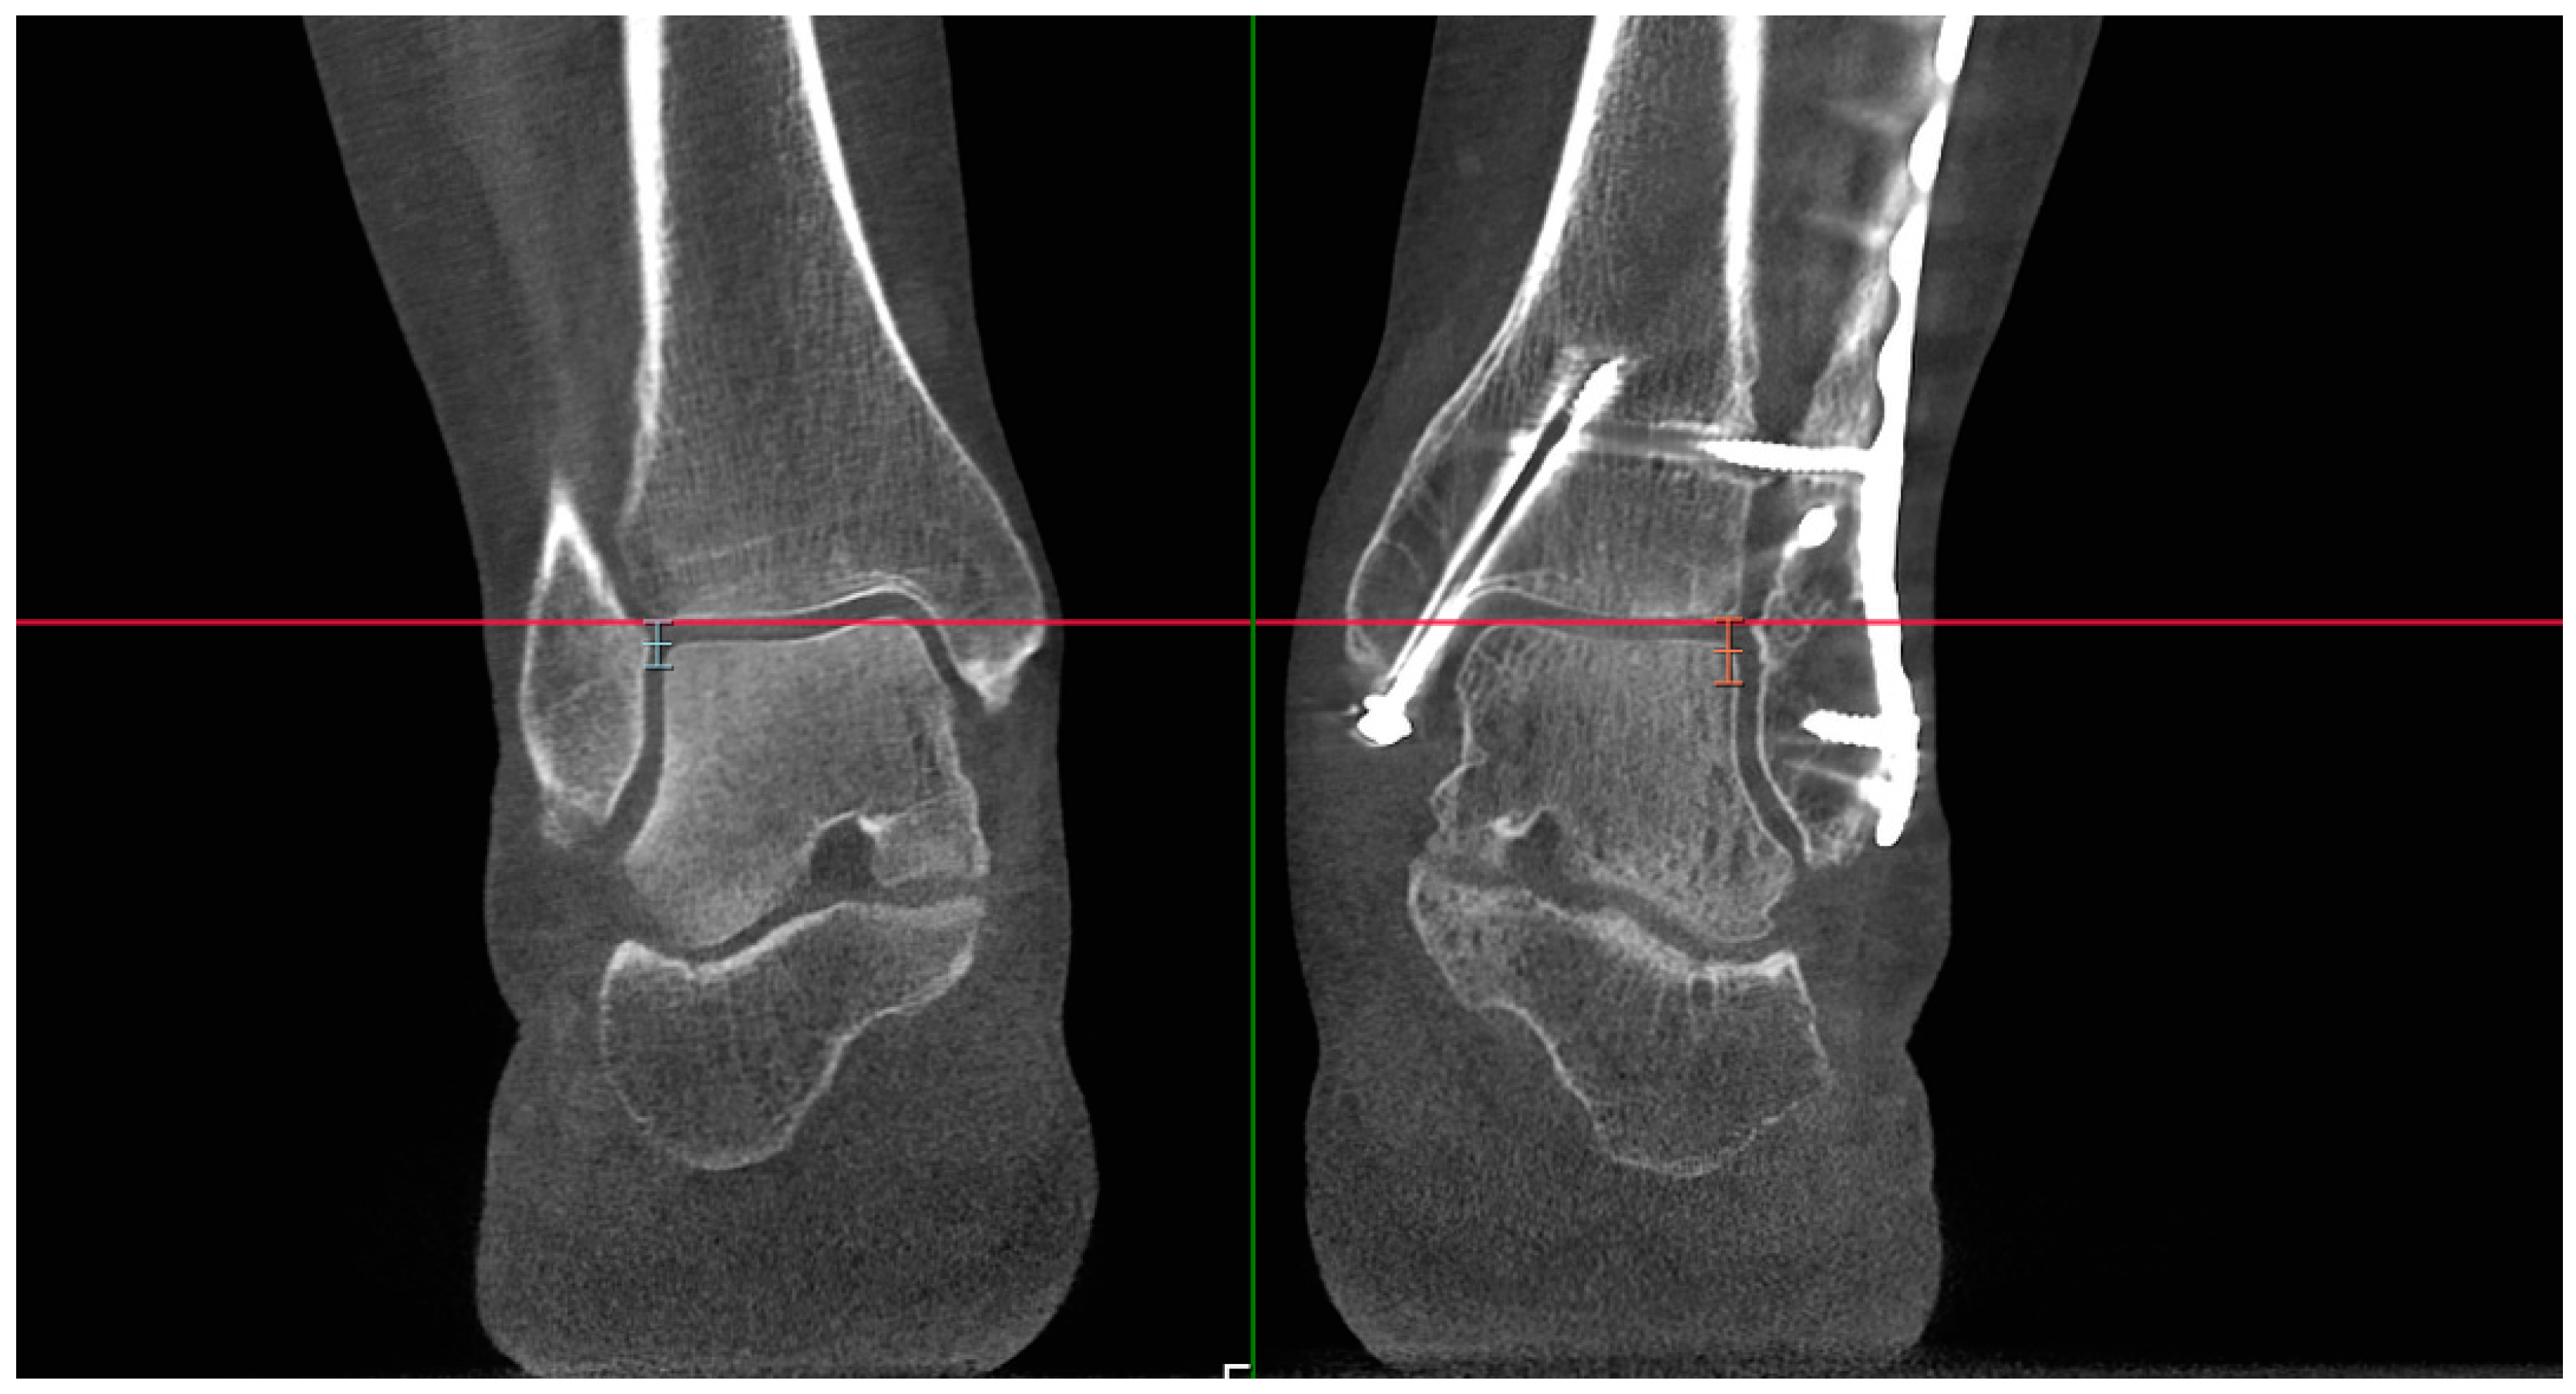

Figure 4. Bilateral presentation of variant 2a of ‘engagement’ shown on both sides with pink lines—the distance between reference Line A (marked blue) and the shortest distance along a perpendicular line to the cortex of the fibula.